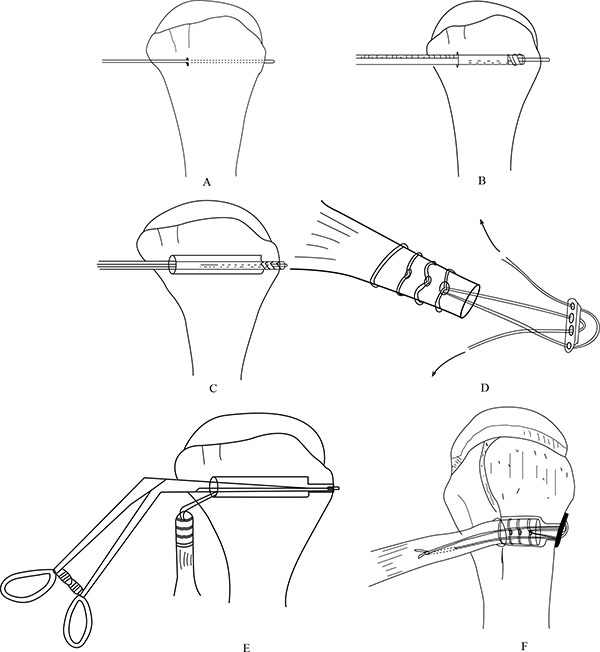

At this stage, we go back to our first incision site to prepare the tenodesis site. The distal part of the bicipital groove (DBG) is identified and cleared off soft tissues. A 2.7mmx 15” guide wire is drilled at an angle of 45º through the center of DBG. Care should be taken to avoid skydiving off the edge of the humeral shaft (Fig. 3B). The guide wire should be stopped as soon as the pin penetrates the posterior cortex (Fig. 4A). This is followed by drilling the anterior cortex over the guide wire with a calibrated cannulated drill, the size of which is the same as the measured diameter of the tendon (in our case, a 7-mm drill for a 7-mm tendon) (Figs. 3C, 4B). Care is taken to only drill up to the posterior cortex without engaging the cortex or plunging through. Depth of this bone tunnel is measured with the aid of a calibrated drill (TD- Tunnel Depth). Usually it is around a 20-25mm tunnel in adults. The hole should be lined up at the base of the biceps groove and cleared of soft tissue. Finally, the posterior cortex is drilled through with a 4.5-mm drill to allow for the passage of the cortical button (Fig. 4C).

A number-5 synthetic polyester suture (Ethibond Excel, Ethicon Inc; Johnson and Johnson, USA) is woven into the proximal biceps tendon using the Krackow technique or whipstitch suture technique (Fig. 3D). The tendon end to the DBG is retrieved again using the smallest size Foleys catheter (Fig. 3E). We used a 4-holed Endo Button without continuous loop (4.0 mm × 12 mm Endo-Button CL Ultra, Smith and Nephew, Andover, MA, USA). One limb of suture from the tendon end was threaded through the central two holes of the Endo Button (inside out – outside in). The other suture end from the tendon was passed through the terminal two holes of the Endo Button in a reverse manner i.e. from outside in – inside out (Figs. 4D, 7, 3F). It is important to make certain that the suture limbs are not tangled.

The Endo Button is loaded onto the Button deployment device and passed through bone tunnel (Figs. 4E, 3G). Once the button clears the posterior cortex, the deployment instrument can be removed while the button deploys itself, locking into place on the posterior cortex. Pulling on the sutures shuttles the LHB tendon into the humerus. The sutures are tensioned until the tendon is in contact with the posterior cortex (Fig. 3H). Finally, we advocate using a free needle to pass one suture through the tendon and tie down to the second suture to reinforce the fixation (Figs. 4F, 3I).